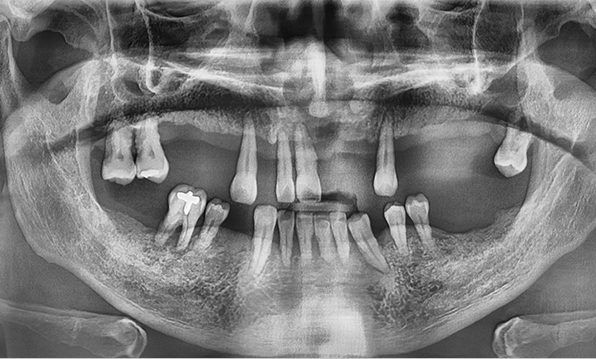

전체 임플란트는 위턱과 아래턱의 교합, 잇몸뼈의 상태 및

얼굴 변화 등 모든 것을 고려해 식립해야 합니다.

서울더자연치과는 3D 디지털 기술의 정밀 진단을 바탕으로

수술 계획을 세워 수술을 집도합니다.

치료기간 : 2021.04.12~2021.09.15